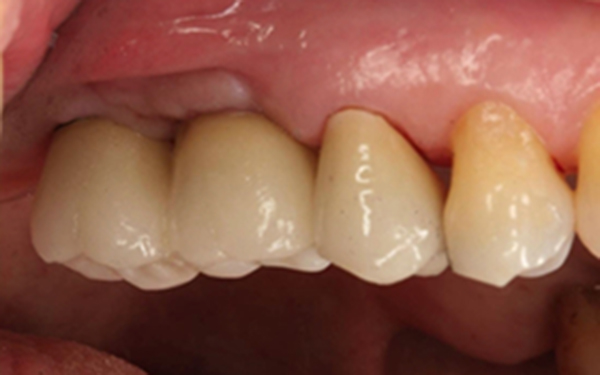

最後裝置假牙

完成照片

完成時X光片可看見新生骨頭